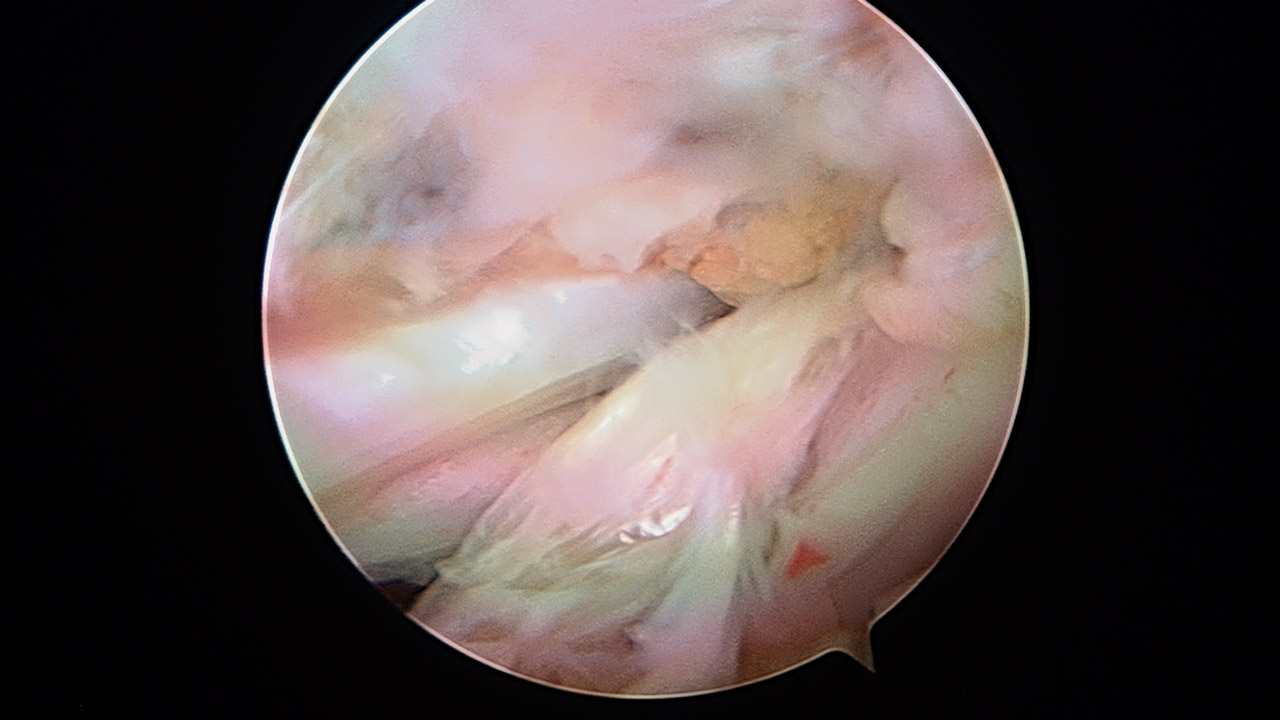

Paso 4: split subescapular

A través del portal M (y de forma similar a la técnica del Latarjet descrita por el Dr. Lafosse)(14), realizamos el split del subescapular, que debe ser lo suficientemente amplio en zona medial para no restringir la rotación externa. En este punto hay que tener precaución con el nervio axilar en la cara anterior del subescapular al hacer la disección medial del mismo. A través del split se recupera la sutura transportadora situada en la glena.